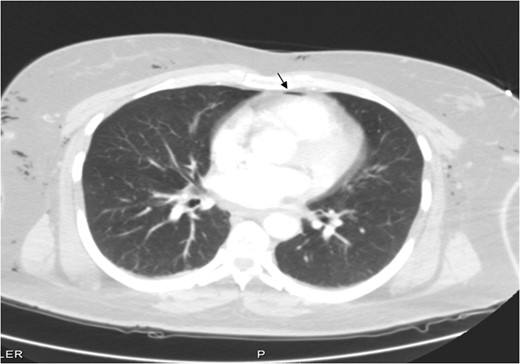

A 46-year-old female, Gravida 3 para 3, all alive, with past medical history of depression, acid reflux and uterine fibroids presented to our emergency unit with acute exacerbation of lower abdominal pain, vaginal bleeding and dizziness, which she had for a month. On examination, her abdomen was soft, with tenderness to right and left lower quadrants. Pelvic examination showed a 14-week uterus, per vaginal bleed and closed cervical os. A repeat sonogram showed the uterus to be 13.9 × 4.8 × 7.1 cm3 with three dominant intramural fibroids. Fundal fibroid measured 3.3 cm, mid posterior uterine fibroid measured 2.2 cm and mid/lower uterine fibroid, 3.8 cm. The central endometrial echo was normal. The right ovary measured ~2.5 × 1.7 × 3.0 cm3 while the left ovary, was 2.5 × 1.9 × 1.7 cm3. Her hematocrit and hemoglobin on presentation were 32% and 11 g/dl, respectively, down from 42% and 14 g/dl a week earlier. She was scheduled for laparoscopic-assisted vaginal supra-cevical hysterectomy with bilateral salpingo-oophorectomy. The operative technique required placing the patient in steep Trendelenburg position and use of a Veress needle through an umbilical incision for insufflation of 3 l of carbon dioxide at a pressure of 15–20 mmHg. All trocal placements were done without complications. Estimated blood loss was 700 ml. The operative time was 7 h (420 min). Surgery was complicated with carbon dioxide overload and retention, with partial pressure of carbon dioxide (PCO2) of 67 mm of mercury (mmHg) immediately post operatively. Patient developed extensive subcutaneous emphysema, and pneumomediastinum (Figs 1–3) on first post-operative Day 1, requiring intubation and mechanical ventilation. Her minute ventilation was increased to wash off the excess CO2. She was sedated and managed expectantly with observation and watchful waiting in the intensive unit. Both subcutaneous emphysema and pneumomediastinum resolved spontaneously by post-operative Day 3 with non-operative treatment. She was eventually discharged in stable condition on post-operative Day 3 and followed up in clinic with no residual issues.

Pneumomediastinum and subcutaneous emphysema as indicated by the arrows.